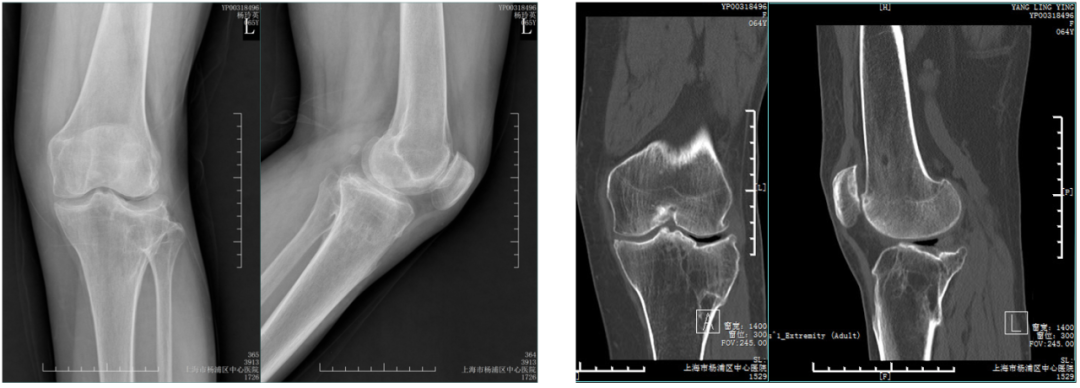

术前X-ray,CT